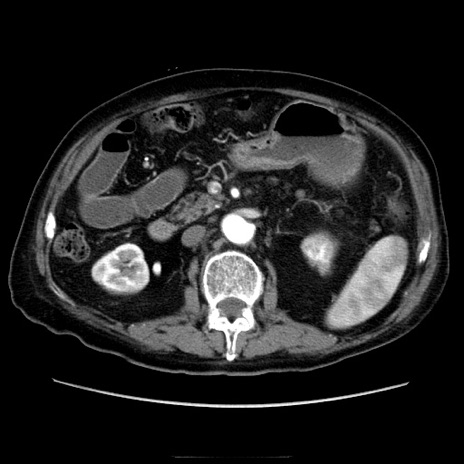

症例21(横断像)

【症例】70歳代男性

【主訴】腹痛

【現病歴】肝硬変・肝細胞癌にてかかりつけの方。約9時間前に食後より腹痛出現。症状が徐々に増悪し、嘔吐出現したため来院。

【既往歴】肝硬変、肝細胞癌(RFA、TACE後)

【身体所見】意識清明、表情苦悶様、BT 36℃、BP 129/78mmHg、P 88bpm、SpO2 97%(RA)、右上腹部から心窩部にかけて圧痛あり、反跳痛なし、筋性防御あり。

【データ】WBC 5800、CRP 0.16